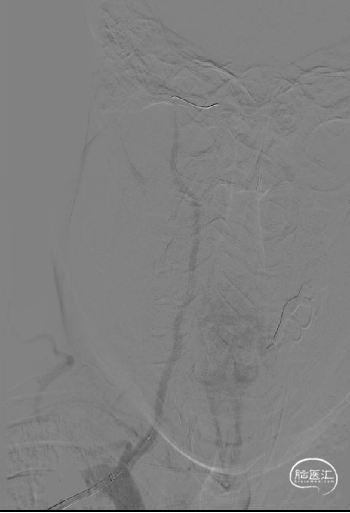

术前脑血管造影示:右侧椎动脉V1段重度狭窄。

患者取平卧位,常规消毒术区皮肤,置无菌单,右侧桡动脉局麻后,行右侧桡动脉Seldinger法穿刺,并置入6F动脉鞘,以180cm超滑泥鳅导丝携单弯管行选择性脑动脉造影。造影结果示:右侧椎动脉V1段重度狭窄。

术前影像